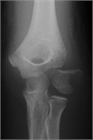

1. 疫学:小児肘骨折の10~20%を占め、平均年齢は6歳。男性が67.4%、左肘の骨折が57.8%。

1. 受傷日に転位が2.0mm未満であった小児上腕骨外側顆骨折23例(2~ 11歳,男14女9)の後向き研究

1. 当院初診日の転位量が2.0mm以上であった6例は手術を行ったが、初診日までの外固定肢位は全例肘屈曲83°以下

1. 初診日の転位量が2.0mm未満であった17例は、前腕回内、肘屈曲96~120°で外固定し、全例骨癒合。可動域も良好。